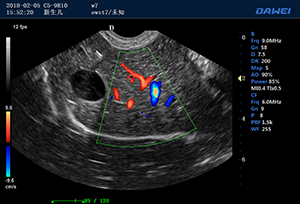

·支持B、C、PW、CW、寬景成像

·適用于各種動物的臨床腹部、胸腔,心臟、肌腱、小器官、眼球、生殖系統等的檢查